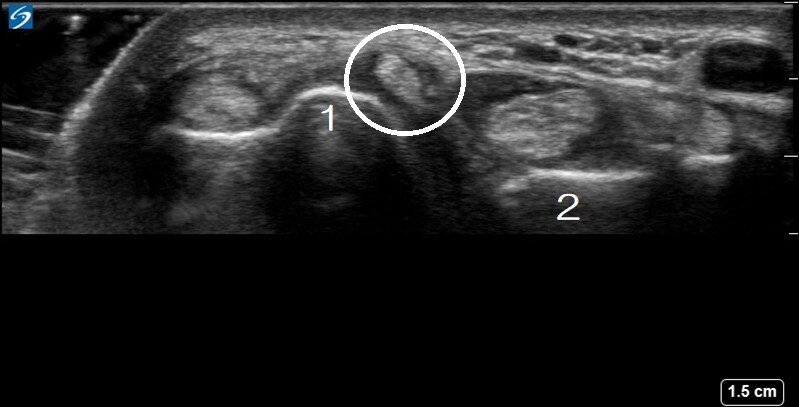

1. Radius

2. Ulna

Circled: Extensor Digiti Minimi, which has a retinaculum beneath and above